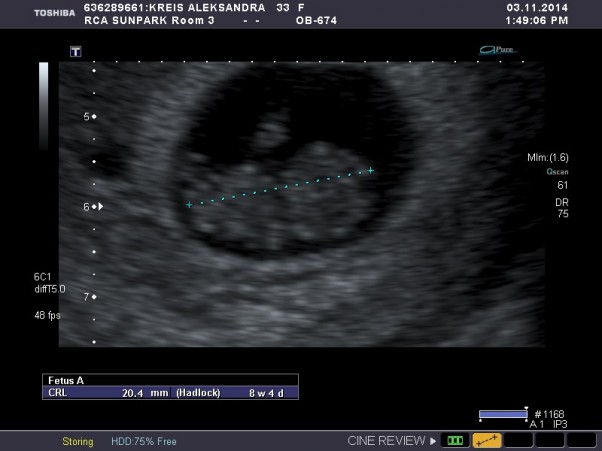

USG w 8 tyg I 4 dniu ciazy, cos pieknego! Niesamowita chwila moc zobaczyc taki wielki - maly skarb ktory w sobie nosze, wspaniay czas lezec i moc patrzec... wspaniay czas....